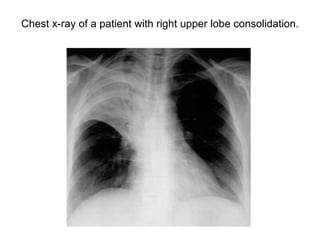

Chest x-ray of a patient with right upper lobe consolidation.

• Indicates that the lesion is intrapulmonary.

• Seen in

– Pneumonia

– Pulmonary edema

– Hyaline membrane disease

– Alveolar cell carcinoma

– Lymphoma

– Radiation pneumonitis